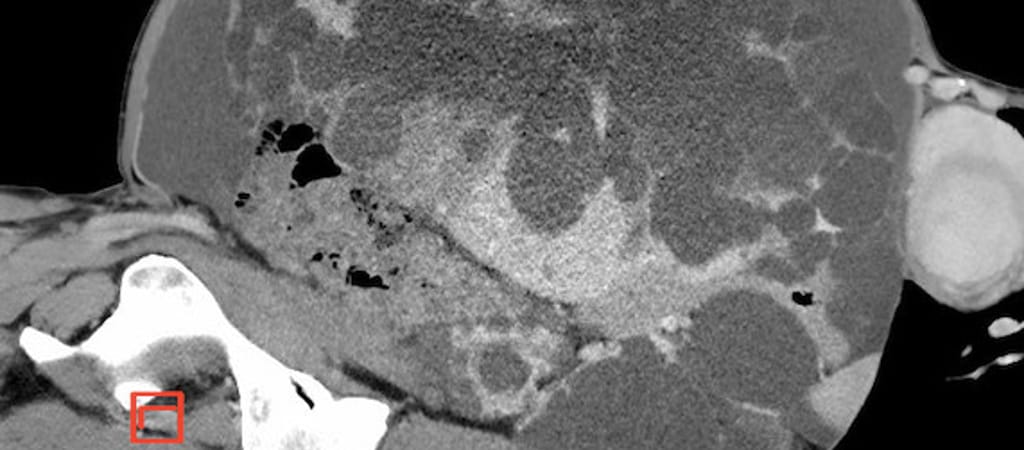

Kioperálták az orvosok egy osztrák nő 17,5 kilogrammot nyomó, úgynevezett policisztás máját Grazban.

Peter Schemmer, a Grazi Egyetemi Klinika munkatársa szerint a múlt héten kioperált szerv valószínűleg az eddig eltávolított legnagyobb policisztás máj Európában.

Az operációval összesen 40 kilogramm súlytól szabadult meg egy csapásra. Betegsége miatt túl sok víz gyűlt össze a hasüregében, a műtét során ezt a folyadékot is eltávolították. (A májbetegség jellemzője, hogy a szervben folyadékkal töltött hólyagok alakulnak ki.)

A policisztás máj meglehetősen ritka. A klinika szerint mintegy 10 ezer emberre jut egy-egy ilyen eset, mely többnyire genetikai eredetű.